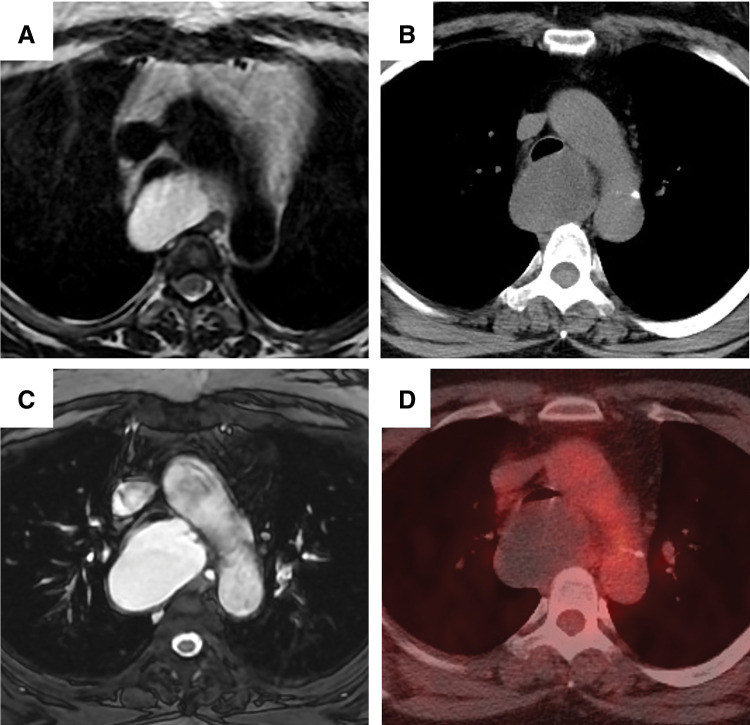

Case presentation: We report the case of a 53-year-old woman who had been under observation for 10 years for an asymptomatic mediastinal mass. The mass enlarged gradually and caused persistent cough along with obstructive ventilatory impairment. Chest CT revealed a 5.5 cm mass compressing the membranous trachea, resulting in tracheal stenosis. MRI revealed a homogeneously high T2 signal within the mass, suggesting a simple cystic nature. PET showed no accumulation of fluorodeoxyglucose in the mass, indicating no malignancy. Based on preoperative diagnosis of a bronchogenic cyst, the patient underwent video-assisted thoracoscopic surgery. Tracheal intubation using a double-lumen tube was challenging due to the tracheal stenosis. Moreover, the membranous trachea compressed by the cyst exhibited white degeneration, suggesting thinning and fragility. Intraoperatively, due to firm adhesion to the membranous trachea, a part of the cyst wall was intentionally left in place to avoid tracheal injury. The inner lining of the residual cyst was cauterized to prevent recurrence. Bronchoscopic findings on POD 7 showed that white degeneration of the membranous trachea remained. Histopathological examination revealed ciliated columnar epithelium and cartilage on the cyst wall, confirming the diagnosis of a bronchogenic cyst.